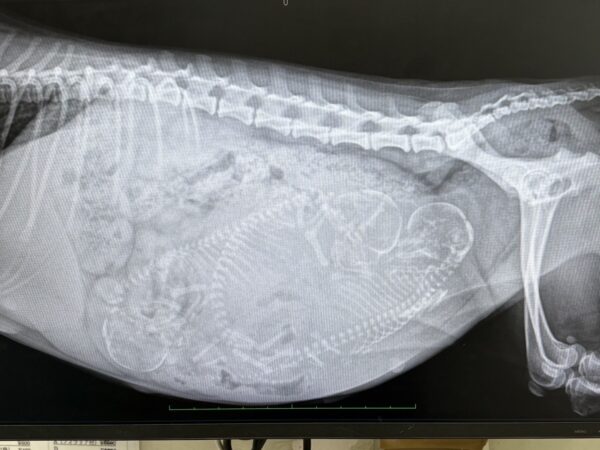

トイプードルの楓ちゃんレントゲン🩻

今週末、出産予定の楓ちゃん、

今日、川野動物病院にレントゲンに行きました❤️

3匹赤ちゃんいました🩷

しっかりもうしてるみたいで、陣痛さえ来たら大丈夫🙆

予定日まで居たらうーん出ないかもになりました😭